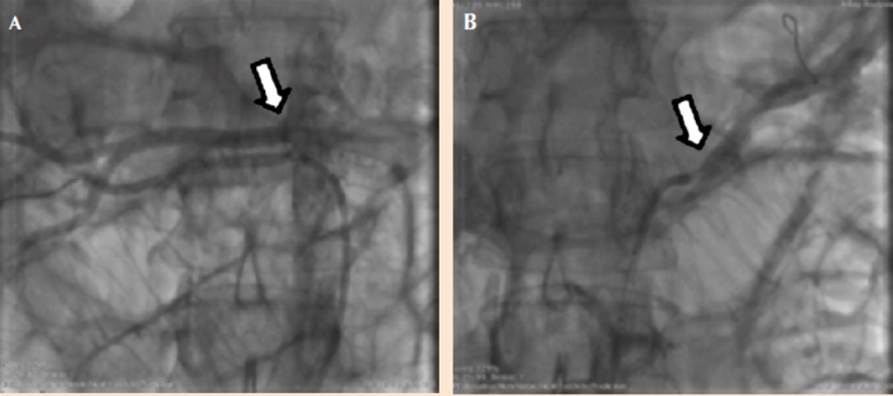

En vista de estos hallazgos, se trató como displasia fibromuscular y se procedió a realizar angioplastia bilateral. Primero de la arteria renal izquierda, predilatándose con un balón 6.0 x 20 mm e implantándose a seguir una endoprótesis vascular de 7.0 x 12 mm sin lesión residual y con flujo normal. Se canuló la arteria renal derecha superior entregándose una endoprótesis vascular directa 5.0 x 12 mm sin lesión residual con flujo normal. Posteriormente se canuló la arterial renal derecha inferior entregándose otra endoprótesis vascular directa de 3.5 x 20 mm sin lesión residual pero con espasmo posterior a la endoprótesis que cedió con 200 µg de nitroglicerina, concluyendo el procedimiento sin complicaciones (Figura 3).

Figura 3 A. Permeabilización con endoprótesis vascular de la arteria renal derecha (principal y accesoria). B. Permeabilización con endoprótesis vascular de la arteria renal izquierda (flecha).